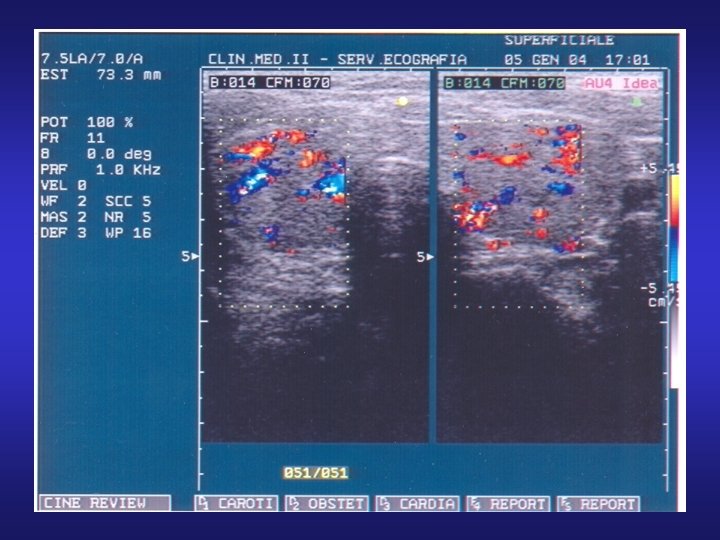

Eco color Doppler di linfonodo superficiale normale: può essere individuato soltanto il peduncolo vascolare

Eco color Doppler di linfonodo superficiale normale: può essere individuato soltanto il peduncolo vascolare all’ilo con presenza di flusso sia arterioso che venoso.